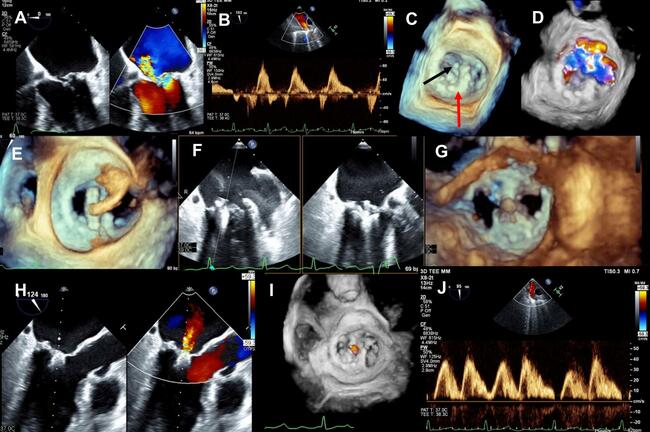

Video 1. Two-dimensional transesophageal echocardiogram demonstrating flail posterior leaflet with severe mitral regurgitation.

Video 2. Three-dimensional view of the mitral valve demonstrating annuloplasty ring with flail segment.

Video 4. Three-dimensional view of the mitral valve demonstrating the advancing of the clip through the annuloplasty ring.

Video 6. Three-dimensional view of the mitral valve (ventricular aspect) demonstrating tissue grasp.